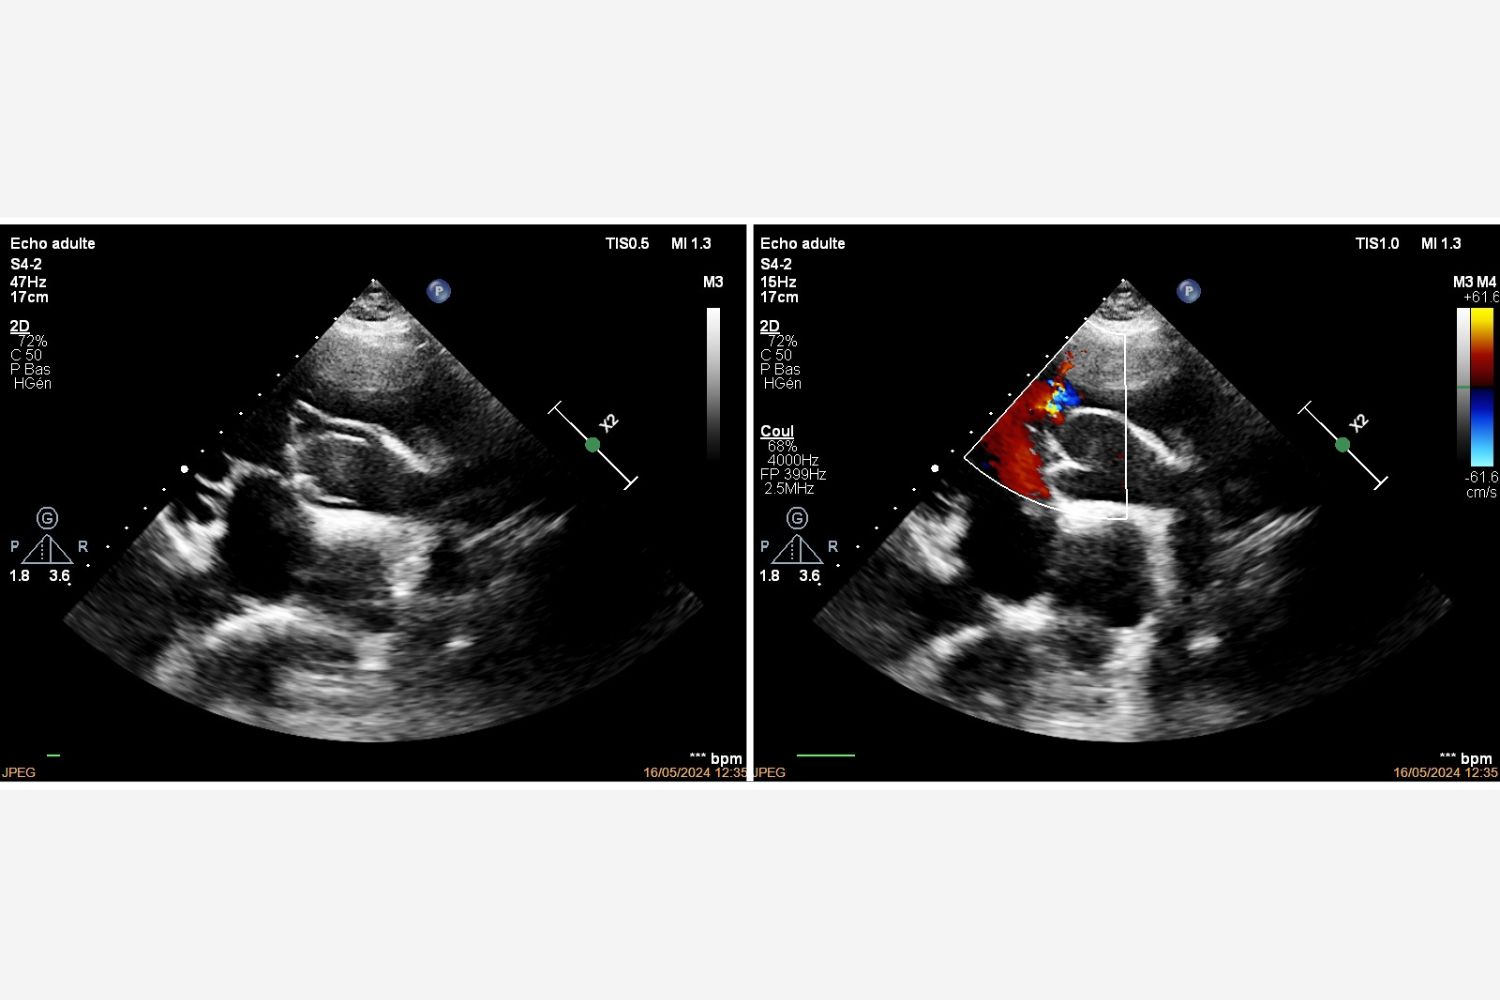

Image of the Week - 17 December 2025

Image of the week